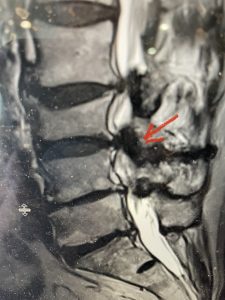

The next patient is a 71 year-old male with a two-year history of low back pain and lower extremity pain, numbness and weakness. His left leg was worse than the right. He had had five epidurals with no improvement. He also had tried physical therapy and medicines but nothing helped. He also felt that over the last three weeks he had gotten worse. He also had recently had some decreased sensation of bladder fullness and difficulty with bowel movements. MRI revealed a very tight L2-5 stenosis with an extruded L3-4 disc fragment (Fig 3).

(Figs 3a) Sagittal (a) and Axial (b) T2-weighted lumbar MRI demonstrating severe spinal stenosis L2-5 (arrow)and extruded disc at L3-4 on axial image (arrow)

He had concentric severe stenosis with severe compression of the lateral recess and foramen at L3-4 secondary to the superimposed disc herniation. The fact that he had gotten worse with subtle cauda equina features with an extremely tight canal, he underwent a decompressive laminectomy. We also augmented his laminectomy with an in situ fusion from L3-5 as he was relatively young, with more time to reform arthritis, and had been unstable enough to extrude a disc fragment. By placing “bone dust” or bone material along the sides of the spine, specifically laying it across the transverse processes after they have been drilled to bleeding bone, you provide an environment where bone formation is induced to connect the segments, stabilize them, and thereby reduce the signal to make more arthritis as that signal is still present despite the laminectomy. What was interesting was that we encountered a large extruded disk fragment that was significantly contributing to his compression which is often not found in patients in this age bracket. Post operatively he had much improvement of leg pain.